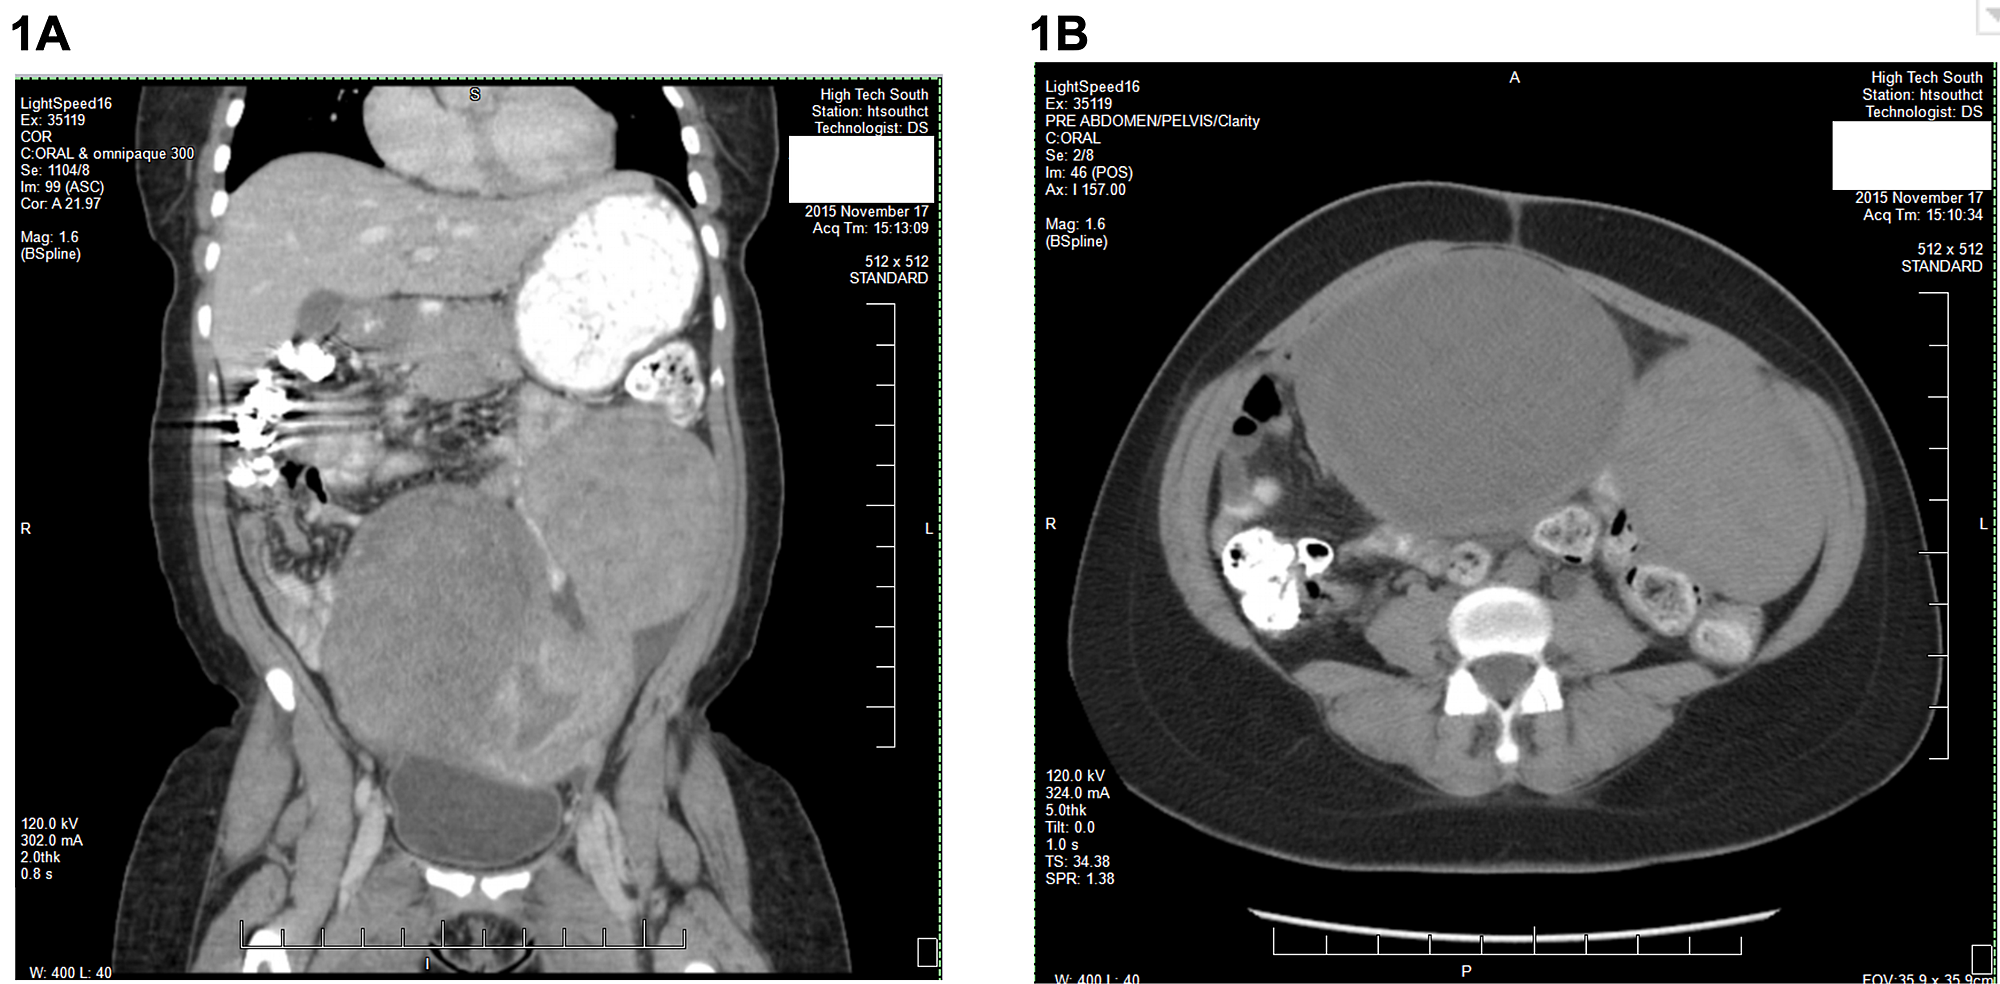

Coronal views of computed tomography scan of abdomen and pelvis with Frozen Abdomen Radiology We report our experience with a patient who presented with frozen abdomen after wound dehiscence due to surgical site infection and. When evaluating the abdomen in the emergency setting, ct and ultrasound are the imaging modalities of choice, mainly because. Differentiate true mechanical obstruction from ileus or constipation. The main aims of imaging in cases of suspected bowel obstruction are:. Frozen Abdomen Radiology.